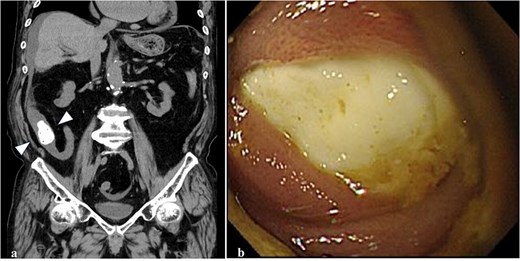

An 89-year-old man with age-related dementia presented with abdominal distension, vomiting, and pain. Physical examination revealed mild abdominal distension and tenderness, especially in the right lower abdomen. Laboratory tests showed an elevated white blood cell count (8430/μl) and C-reactive protein (6.39 mg/dl). Abdominal CT revealed a 30-mm high-density mass in the terminal ileum, with dilated proximal intestines but no signs of intestinal ischemia or free air (Fig. 1a). Based on these findings, the patient was diagnosed with intestinal obstruction due to an FB. Colonoscopy showed a hard, whitish FB 20 cm proximal to the ileocecal valve, which could not be retrieved with a snare (Fig. 1b). Surgery was planned for the second day of hospitalization.

Abdominal CT and colonoscopy. (a) A highly dense mass with fine, low-density spots inside the lumen of the terminal ileum (arrowhead) on the colonal slice of plane CT. (b) The ileum lumen 20 cm proximal from the ileocecal valve was completely occupied by a whitish FB with a hard elasticity and smooth surface when visualized using a colonoscope.